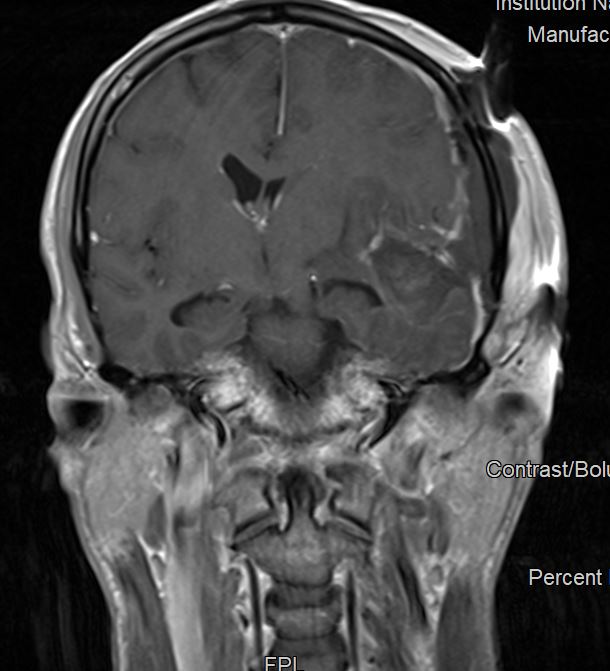

Η μετεγχειρητική μαγνητική τομογραφία ανέδειξε πλήρη εξαίρεση του όγκου.

Η μετεγχειρητική πορεία του ασθενούς ήταν ανεπίπλεκτη με πλήρη αποκατάσταση των συμπτωμάτων και ο ασθενής εξήλθε την 4η μετεγχειρητική ημέρα.